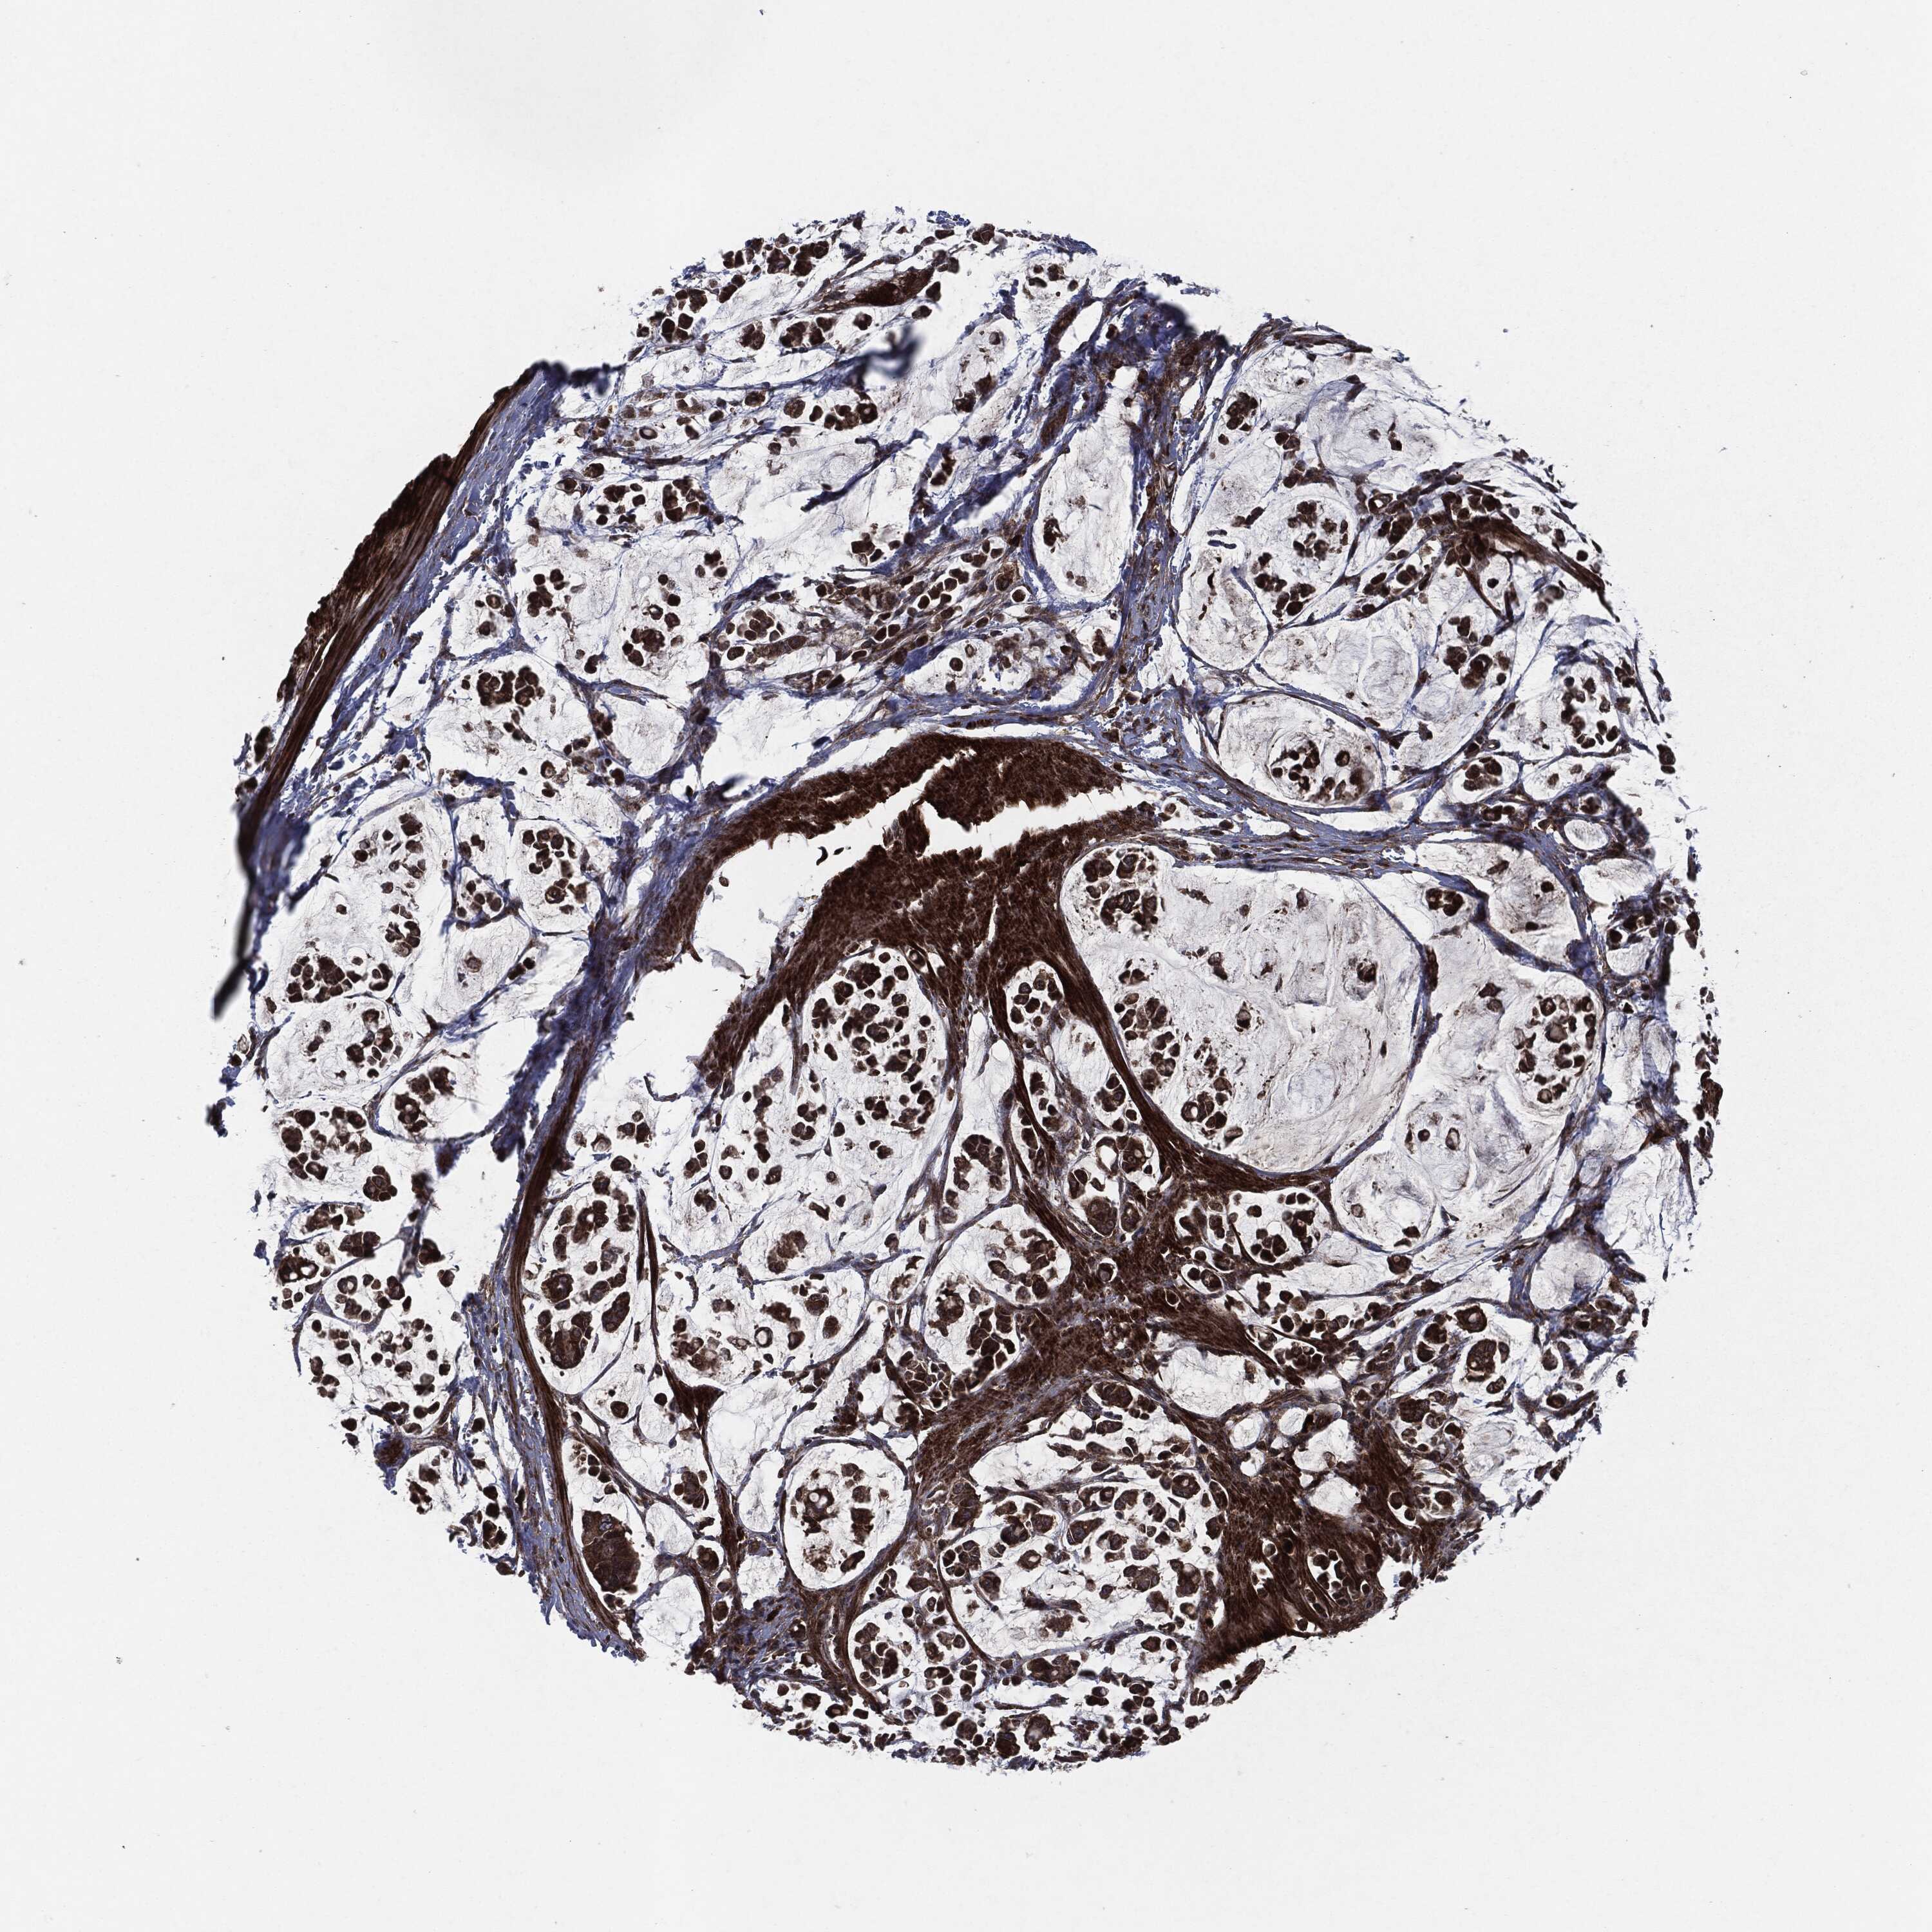

STOMACH CANCER - Protein expressioni

A mouse-over function shows sample information and annotation data. Click on an image to view it in a full screen mode. Samples can be filtered based on level of antibody staining by selecting one or several of the following categories: high, medium, low and not detected. The assay and annotation is described here.

Note that samples used for immunohistochemistry by the Human Protein Atlas do not correspond to samples in the TCGA dataset.

Antibody stainingi

Antibody staining in the annotated cell types in the current human tissue is reported as not detected, low, medium, or high, based on conventional immunohistochemistry profiling in selected tissues. This score is based on the combination of the staining intensity and fraction of stained cells.

Each image is clickable and will lead to virtual microscopy that enables deeper exploration of all samples and also displays staining intensity scores, fraction scores and subcellular localization as well as patient and tissue information for each sample.

Antibody HPA002640

Antibody CAB019291

Antibody CAB080384

Staining

High

Medium

Low

Not detected

Intensity

Strong

Moderate

Weak

Negative

Quantity

>75%

75%-25%

<25%

None

Location

Nuclear

Cytoplasmic/membranous

Cytoplasmic/membranous,nuclear

Adenocarcinoma, NOS

Adenocarcinoma, High grade